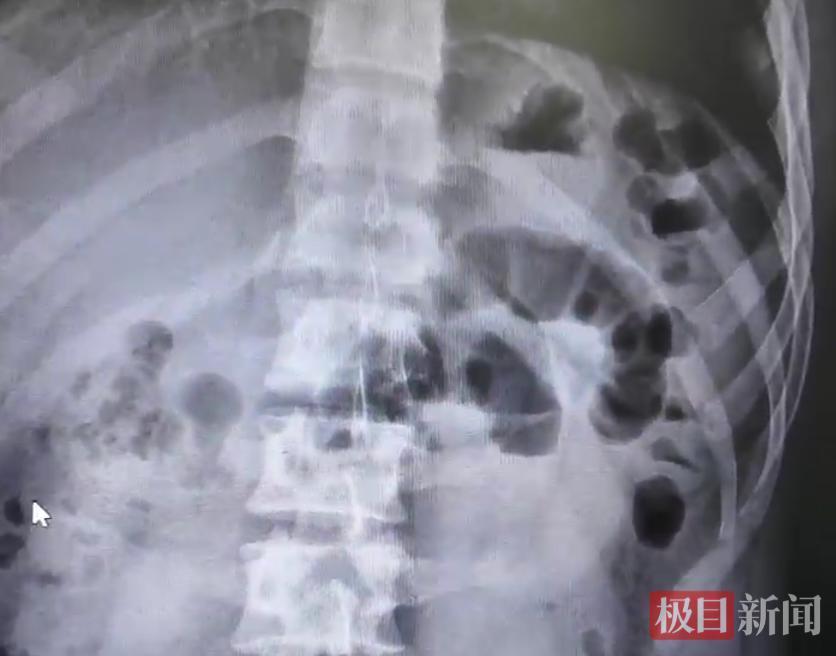

CT查验(受访者供图)

历程腹部CT查验,李阳被确诊为典型小肠抨击,病因恰是短时老实过量进食胡萝卜,肠说念堵塞。